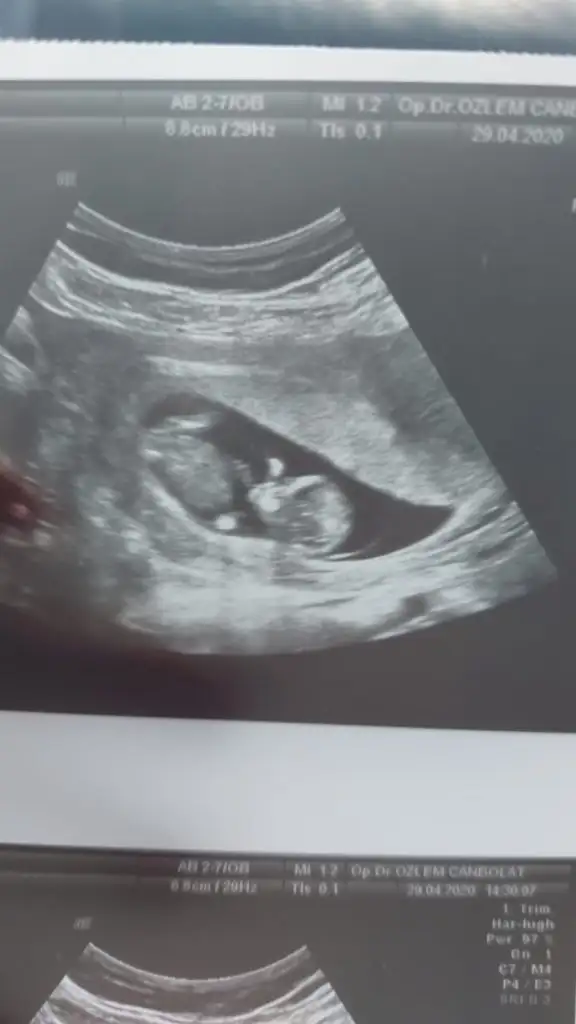

dr soylemeden siz gorun genital nub teorisi ( bebegin cinsiyeti)

Arkadaşlar lutfen tahmin eder misiniz

Eklentiler

Kızlar benim nub teorisi tuttu kızım olacak inşallah 🤗 Bu ara isim arayışındayız isim önerileriniz varsa alırım valla 😍